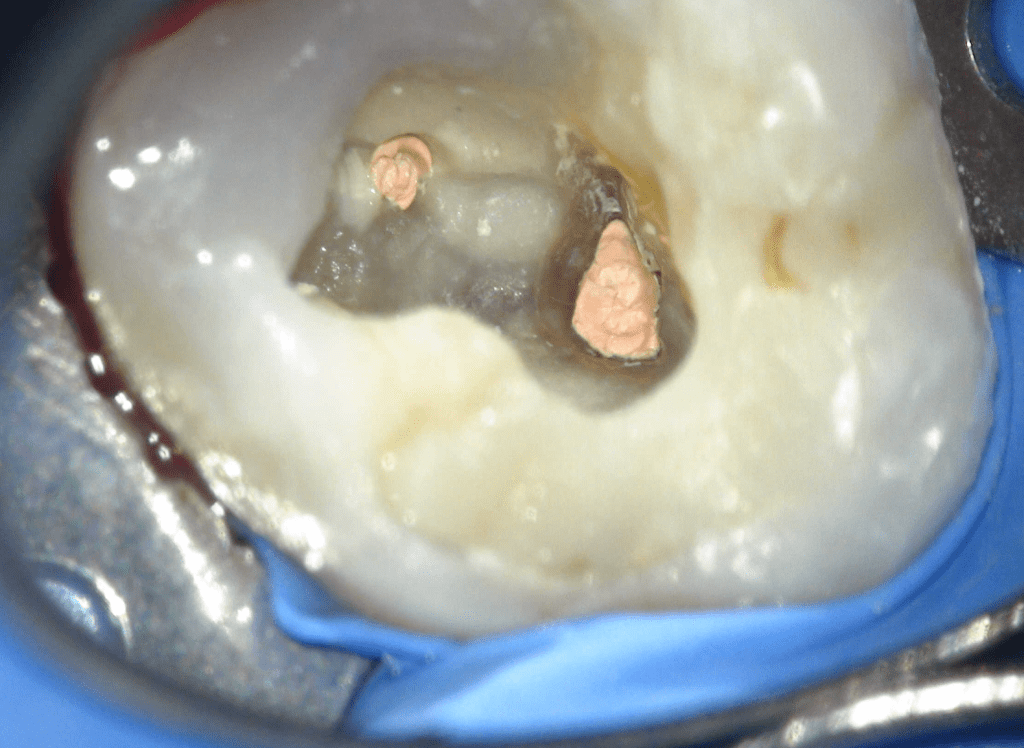

Fisura, remoción amalgama para explorar